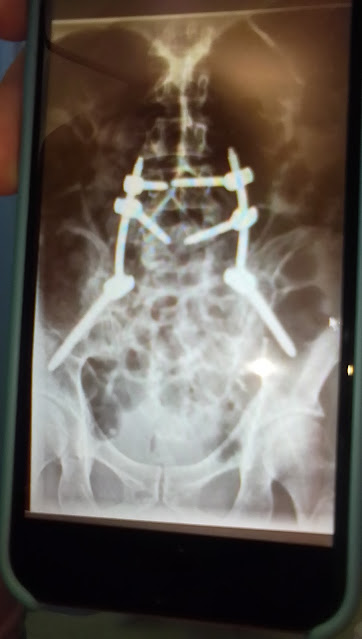

Photo hasil X-ray saya sesudah operasi TULANG EKOR PATAH 10 September 2023 di rumah sakit Royal Perth hospital di Perth City Western Australia.

10 September 2023 saya di operasi TULANG EKOR PATAH di rumah sakit Royal Perth hospital. Spinal cord injury. Dokter pasang plat besi di kiri dan kanan untuk menahan tulang belakang saya. Saya tidak bisa Buang Air Kecil normal. Saya Buang Air Kecil kencing pakai kateter sampai sekarang. Waktu jam tidur saya bangun banyak Kali untuk buang air kecil pakai kateter. Saya tidak bisa tidur nyenyak. Di Siang Hari dan Malam Hari saya tidak bisa kontrol Buang Air Kecil mendadak tiba tiba sehingga baju saya basah dan lantai kotor . Saya sibuk membersihkan lantai dan mencuci sampai sekarang.

3. Operation September 10, 2023 My TAILBONE IS BROKEN. SPINE INJURY. The doctor installed metal plates on the left and right sides to hold my spine. I URINATE using a CATHETER every 4 hours 6 times a day.